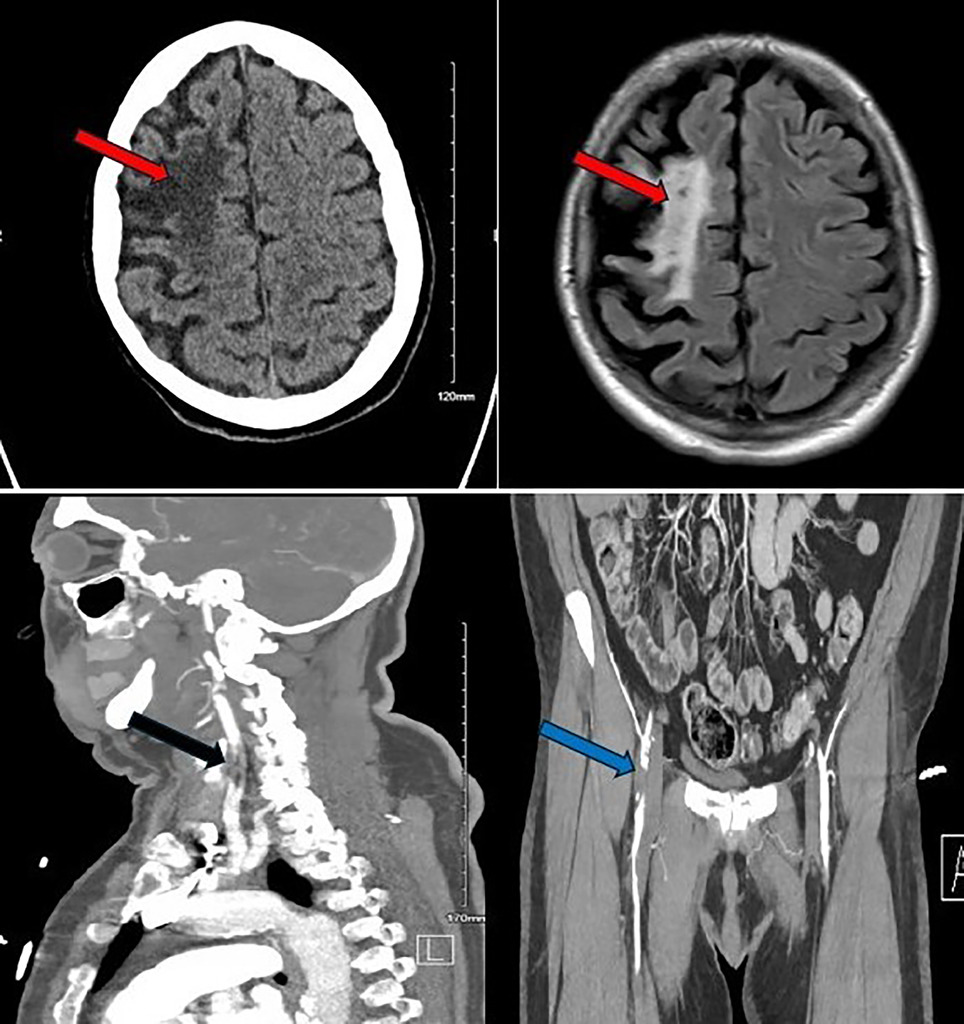

Нейровізуалізація:

КТ/МРТ головного мозку — старий інфаркт у ділянці правої середньої мозкової артерії, без свіжих змін дифузії.

КТ-ангіографія — оклюзія правої внутрішньої сонної артерії, помірний стеноз лівої М2.

КТ-ангіографія грудної клітки, черевної порожнини та таза — виражений атеросклероз, оклюзія правої зовнішньої клубової артерії.